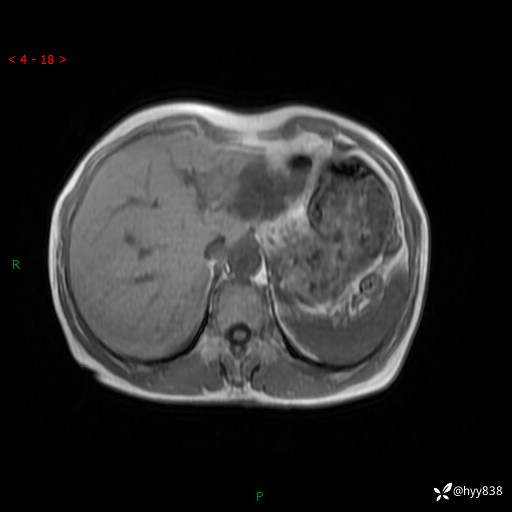

老年女性,偶然发现肝脏占位,综合各个序列,你考虑什么---结果公布

主诉:发现肝脏占位性病变2天

简要病史:患者2天前因“腰疼”至当地医院就诊时发现肝脏左叶占位性病变,无发热、畏寒,无皮肤黄染,无腹痛、腹泻,无恶心、呕吐、厌油等不适,今进一步诊治遂来我院就诊,门诊以“肝脏占位性病变性质待查”收入我科。 起病以来,患者精神、睡眠一般,饮食欠佳,二便正常,体力、体重无明显减轻,

临床诊断:肝占位

治疗经过:手术

肝脏MRI平扫(同反相位)

T2WIfs+DWI

增强(动脉期+静脉期+延迟期)